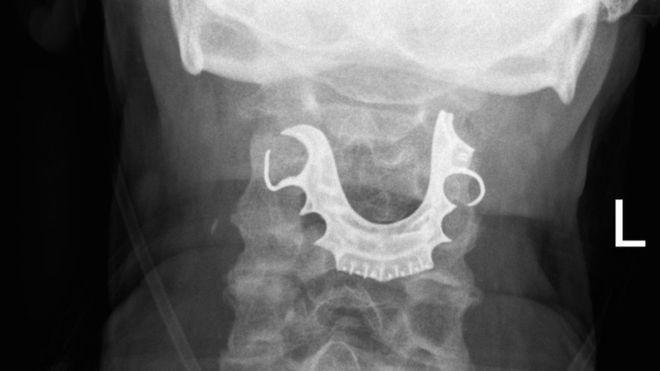

عَلق طقم أسنان أحد المرضى في حلقه أثناء خضوعه لعملية جراحية عادية، وظل مفقودا لثمانية أيام.

ولكن لما عاد الرجل إلى المستشفى بعد يومين، فحص فريق الأطباء حلقه وحنجرته ليجدوا شيئا شبه دائري يقبع على أحباله الصوتية.

ثم لم يلبث أن أخبر الأطباء عن فقدانه طقم أسنانه أثناء إقامته في المستشفى وخضوعه للجراحة.